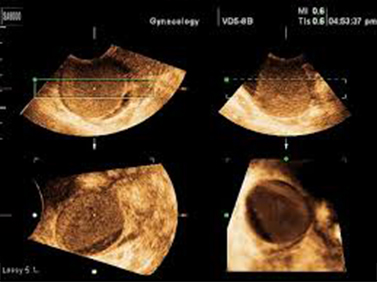

Όταν αναγνωρισθεί η περιοχή ενδιαφέροντος, τίθεται πλαίσιο οριοθέτησης και με σταθερή την υπερηχογραφική κεφαλή αρχίζει η εξέταση. Γίνεται αυτόματη σάρωση 360ο της περιοχής ενδιαφέροντος. Το τελικός αποτέλεσμα είναι η παρουσία 3 πλάνων, τα οποία μπορούν να μετατοπισθούν ή να περιστραφούν γύρω από τους άξονες x, ψ, z. Ο ανασχηματισμός των 3 εικόνων και η τελική σύνθεση μιας μόνο εικόνας προσφέρει ακριβέστερη μορφολογική εκτίμηση του όγκου του σώματος της μήτρας χωρίς να απαιτείται ιδιαίτερος χρόνος, μειώνοντας παράλληλα την δυσφορία αναμονής της ασθενούς.

Τα 3 πλάνα που εμφανίζονται στην οθόνη είναι:

α) το άνω αριστερό πλάνο (στεφανιαίο), «α», β) το άνω δεξιό πλάνο (οβελιαίο), «β», γ) το κάτω αριστερό πλάνο (εγκάρσιο), «γ». Στο κάτω δεξιό πλάνο εμφανίζεται η εικόνα «δ» μετά από τροποποίηση και επεξεργασία των 3 εικόνων («α», «β», «γ»).Για πληρέστερη αξιολόγηση του υπό εξέταση οργάνου και την επίτευξη του όσο το δυνατόν καλυτέρου αποτελέσματος απεικονιστικής ευκρίνειας, γίνεται χρήση ειδικών μεθόδων (modes):